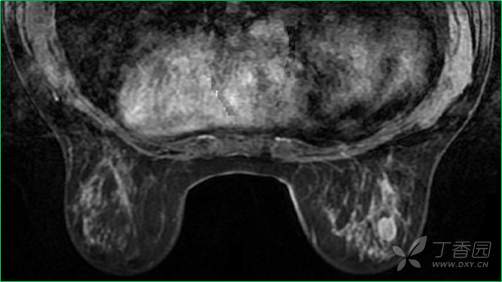

T1WI增强晚期

乳腺MR:左乳外上象限见T2WI高信号肿块影,大小约12mm×10mm×13mm,肿块为卵圆形,边缘模糊不规则;内部强化略不均匀;TIC曲线初始相呈快速强化,延迟期呈平台型;DWI呈高信号,ADC值为 0.000698 mm2/s。

因肿块边缘不规则,内部强化不均匀, TIC曲线初始相呈快速强化,延迟期呈平台型;DWI呈高信号,ADC值较低,考虑左乳外上象限肿块恶性不除外,BIRADS 4类。